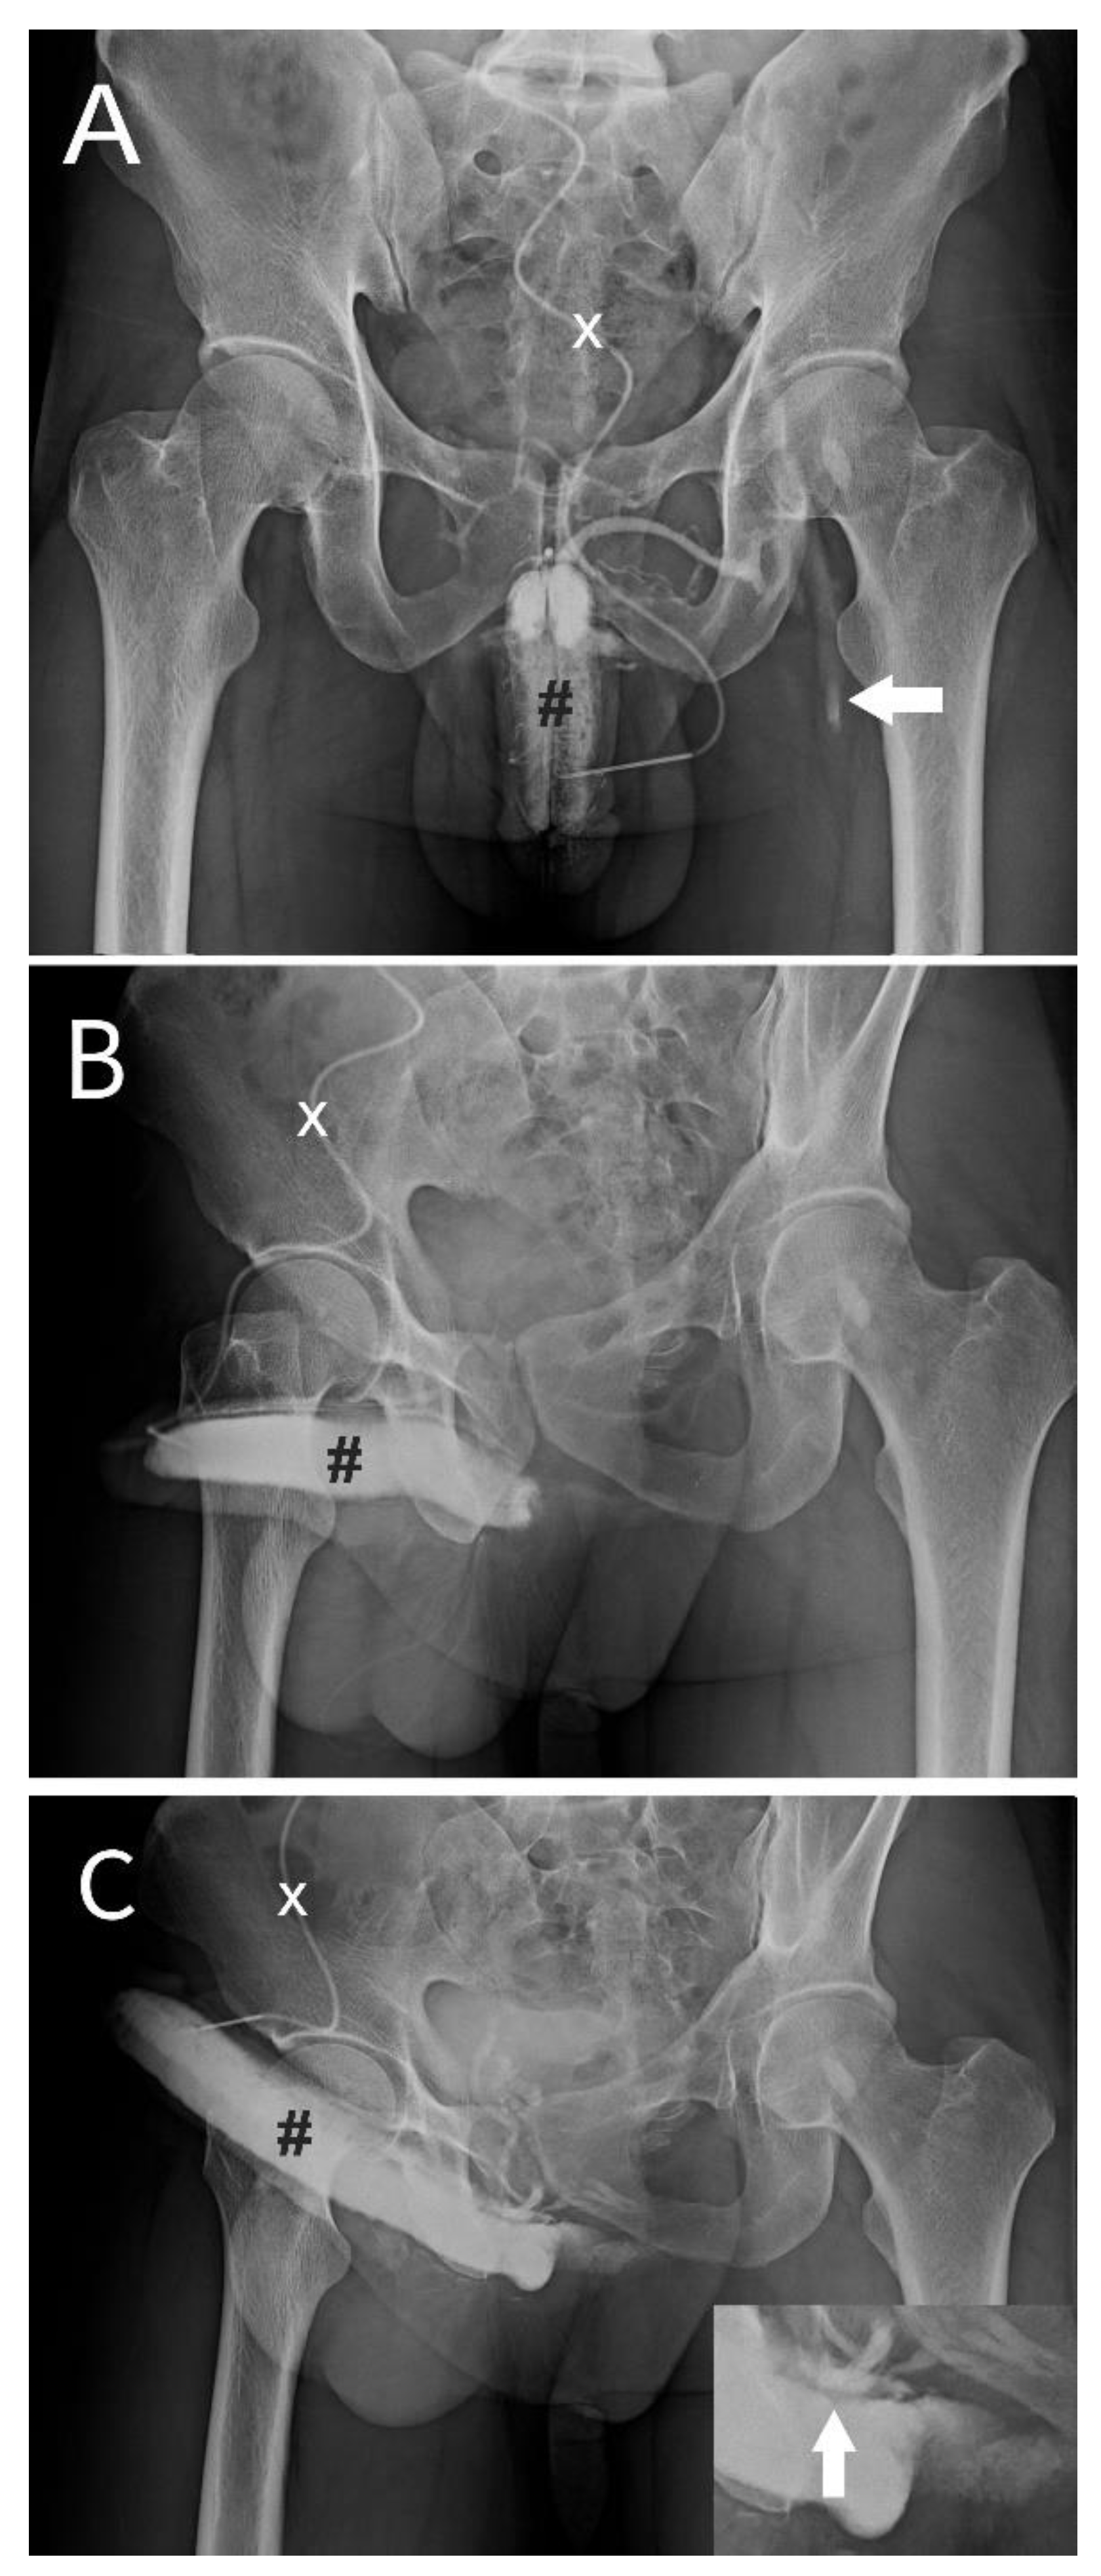

Multiplanar investigations were conducted, and no isolated contributable factor was found elsewhere before consulting our institute. Therefore, all patients were primarily diagnosed with dual cavernosography in which a pilot cavernosograpy disclosed the penile venous anatomy (

Figure 1A, B), a PGE-1 test was performed in-between, and a pharmaco-cavernosography proved a veno-occlusive dysfunction (VOD) (Figure C). In addition, Doppler sonography was utilized if there was no full erection during the PGE-1 test (n=5). Finally, 18 patients underwent PVS and FPGE surgery on an ambulatory basis, and the remaining 13 men were unaffordable for surgery.

Dual cavernosography disclosing veno-occlusive dysfunction is suitable for venous stripping in a 33-year-old patient. A) The pilot cavernosogram was obtained via an anterior-posterior view. After a 19G scalp needle (white cross) was inserted in the corpora cavernosa (black pump), at the same time, a 10-mL diluted iohexol solution was injected intracavernously, resulting in the immediate opacification of the erection-related vein. Note the corporeal drop of blood drained into the left femoral vein (white arrow). B) A 30-degree oblique view of a further 10-ml solution was injected. Note the venous drainage was too fast to opacify the left penile crus. C) A pharmaco-cavernosogram was obtained 10 min after 20 mg of prostaglandin E1 (test) was intracavernous injected (white star). D) The bulking of drainage veins was prominent despite a rigid erection attained (white arrow, inserted film). Thus, a veno-occlusive dysfunction was documented.